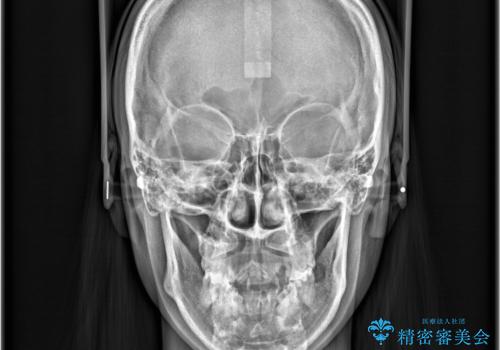

- 八重歯と口元が出ていることを主訴に来院されました。

レントゲンの検査において、前歯も外側に傾いてる結果であったため、上下左右の小臼歯を抜歯して配列を行いました。

歯の動きも良く短期間で治療を終えられたため患者さんにも大変満足していただきました。